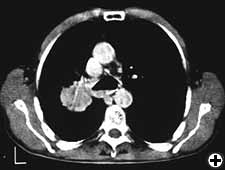

Carinal resection is a complex and aggressive procedure for the treatment of bronchial tumors involving the carina, the tracheo-bronchial angle or the distal portion of the trachea (Figure 1). The airway is reconstructed by anastomosis of the opposite main bronchus (tracheal sleeve pneumonectomy) or both bronchi (isolated carinal resection) to the lower trachea (Figure 2). The most common indication for a sleeve pneumonectomy is a tumor involving the origin of right main bronchus or extending into the lower trachea. Left sleeve pneumonectomy is rarely indicated since the left main bronchus is considerably longer than the right one and, in the case of carinal infiltration, tumor usually invades the structures in the subaortic space as well, which frequently implies inoperability. An isolated carinal resection and reconstruction may be applicable for centrally located, low grade and small tumors of the carina not extending so far to the main bronchi. Carinal resection represents a challenge for thoracic surgeons and anesthesiologists related to demanding intraoperative airway management, the technique of anatomic reconstruction and the risk of significant postoperative morbidity, mortality and poor long-term outcome [11].

Cardiac function is assessed based on a physical examination, electrocardiography, and transthoracic echocardiography in all patients. Radiological work-up includes standard chest X-ray, total body CT-scan, bone scintigraphy and PET scan, where indicated. All patients should be submitted to rigid bronchoscopy (Figure 3) and sometimes to virtual bronchoscopy (Figure 4) to precisely assess the extent of invasion and the required resection. Mediastinoscopy (in case of malignant tumors), performed at the time of planned resection, may be useful to discover potentially involved lymph nodes, to evaluate the mediastinal and extraluminal spread of the neoplasm and to dissect the pretracheal plane, enhancing the mobility of upper trachea and reducing the risk of recurrent laryngeal nerve injury.